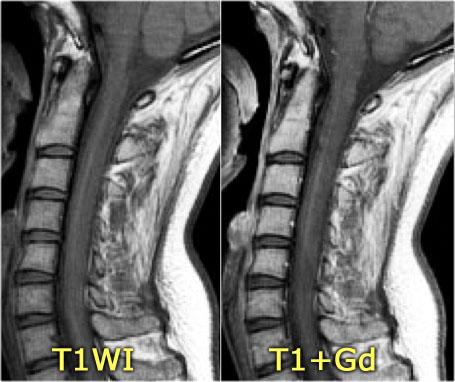

Đây là hình ảnh của một trường hợp TM điển hình.

Có tăng tín hiệu đa đoạn trên STIR và chuỗi xung T2W kèm theo phù nề nhẹ.

Phần lớn tủy sống trên đường kính ngang bị tổn thương.

Không có ngấm thuốc tương phản từ, đây thường là đặc điểm thường gặp trong TM.

Đôi khi có thể thấy ngấm thuốc dạng vá không đều.

Khi có ngấm thuốc tương phản từ, việc phân biệt TM với u tế bào hình sao (astrocytoma) có thể rất khó khăn.

Bên trái là hình ảnh của bệnh nhân nam 60 tuổi mắc u tế bào hình sao.

Bệnh nhân nhập viện với đau vùng ngực và rối loạn cảm giác chi dưới trái, tiếp theo là liệt nửa người trái.

Có tăng tín hiệu đa đoạn trên chuỗi xung T2W kèm phù nề nhẹ, tương tự như hình ảnh đã thấy trong các trường hợp TM.

Trên CE-T1W có vùng ngấm thuốc tương phản từ.

Vùng ngấm thuốc có hình thái nghiêng về u hơn, nhưng việc phân biệt vẫn còn khó khăn.